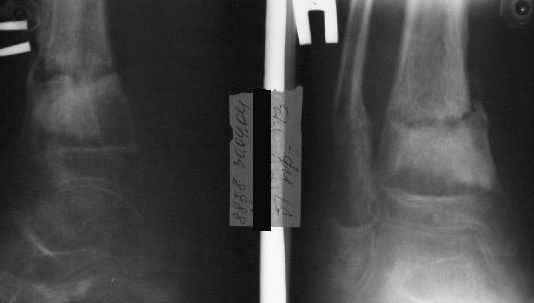

Фиксация

в гипсе

Промежуточный